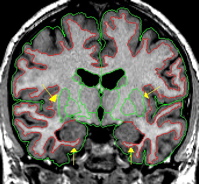

| General Description The cerebral white matter is comprised of any area of the brain with a high concentration of axons covered in myelin. Because myelin is made of lipid, it has a white appearance in MRI scans. During segmentation the white matter is separated from the cortex and subcortical structures using the histogram function. There is a different white matter parcellation program used to divide the white matter into its constituents. | |

| Procedure Segmentation  If the white matter appears continuously on the MRI scan, but your histogram does not give you a continuous outline, manually draw in a strip a white matter between the two lobes. Also, if the two lobes are connected (share the same exterior outline) the white matter must be continuous. By convention and by anatomy, cerebral white matter should never extend through the cortical ribbon. Radiologically speaking, an image may be produced in which partial voluming contributes to the illusion that the white matter extends to the edge of the cortex, though anatomically, this does not occur in the normal brain. Manually edit as necessary to ensure the white matter does not touch the cerebral exterior along the edges of the brain. White matter does extend to the medial exterior border where the corpus callosum is located. This should be apparent with your histogram, if this is not apparent, manually edit to include all of the corpus callosum. | |

|  | Be sure to have continuous white matter lateral to the putamen and below the hippocampus. If necessary, manually draw these borders. Also, if a temporal lobe connects to a frontal lobe, then white matter must exist along that connection. If necessary, manually draw in a thin strip of white matter.